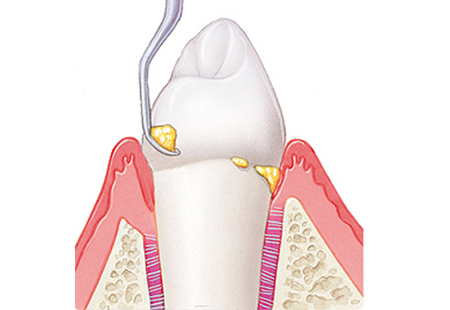

歯周病の進行度を測るために、専用の器具(プローブ)を用いて歯周ポケットの深さを測ります。

スケーリング(歯石除去)

歯の表面にこびりついた石のように硬い「歯石」を取り除きます。

歯石は細菌の温床であり、ハミガキでは絶対に落ちません。

超音波スケーラーなどを用い、歯ぐきの上に見えている汚れを一掃します。

ルートプレーニング(歯ぐきの中の清掃)

歯ぐきの奥深く(歯周ポケット内)に隠れた歯石や、毒素に汚染された歯根の表面を滑らかにする処置です。

ここをツルツルに整えることで、細菌の再付着を防ぎ、歯ぐきが歯に再び密着するのを助けます。